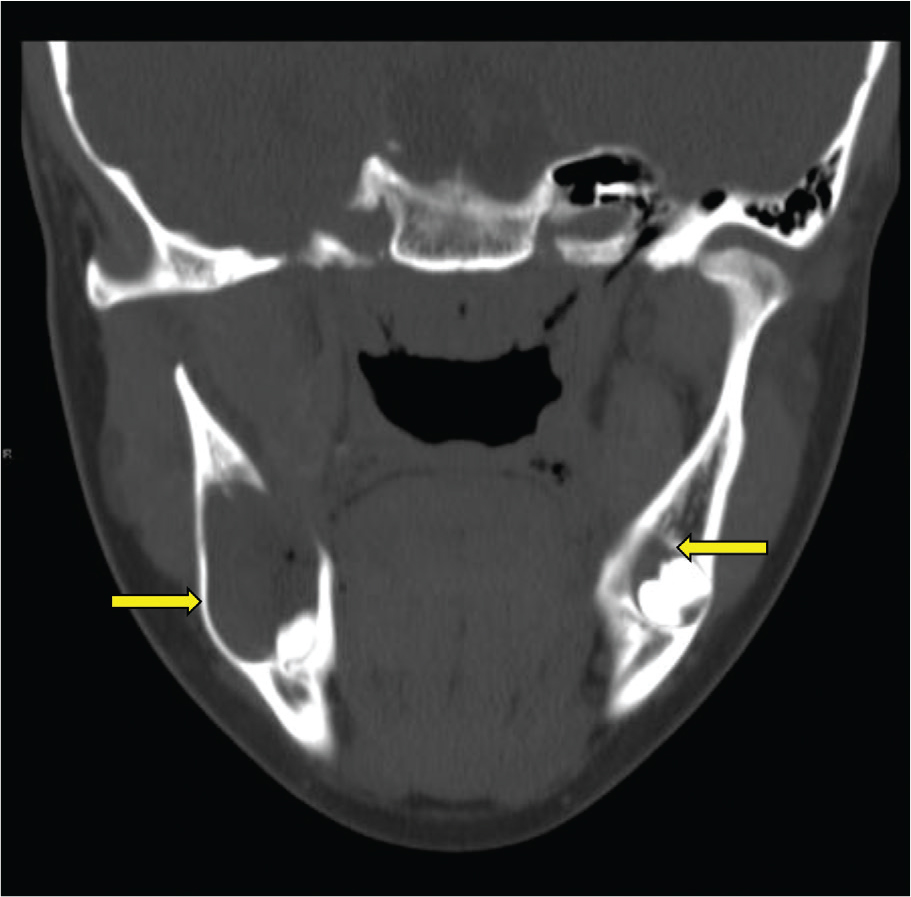

As part of the workup for the dental findings, she had a computed tomography (CT) of the head, which identified a calcified falx cerebri (Figure 2). A CT of the jaw (Figure 3) revealed multiple mini cysts and a large cyst in her lower jaw. Surgery removed a cyst from the right mandibular body and ramus associated with impacted tooth #31 pathology was consistent with an odontogenic keratocyst. After being seen by the surgeon, she was referred for genetic testing. Her past medical history was notable for a broken arm, benign hydrocephalus at around 8 months of age for which she had magnetic resonance imaging performed.

Fig. 3. Coronal maxillofacial CT demonstrating expansile cystic lesions in the bilateral mandible compatible with multiple odontogenic keratocysts. CT: computed tomography.